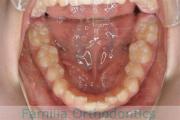

上の前歯の並びが気になるのできれいにしたい、ということで来院されました。マウスピース型矯正装置のひとつ、インビザライン/InvisalignR(薬機法および医薬品副作用被害救済制度の対象外)を用いて治療しました。

非抜歯で2年弱、20回程度の通院で治療が完了しました。

マウスピース矯正は、患者さんの協力に治療結果が左右されるところはリスクと言えるかもしれません。